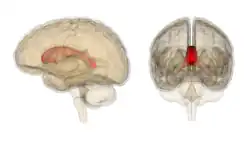

The corpus callosum (Latin for "tough body"), also callosal commissure, is a wide, thick nerve tract, consisting of a flat bundle of commissural fibers, beneath the cerebral cortex in the brain. The corpus callosum is only found in placental mammals.[1] It spans part of the longitudinal fissure, connecting the left and right cerebral hemispheres, enabling communication between them. It is the largest white matter structure in the human brain, about 10 cm (3.9 in) in length and consisting of 200–300 million axonal projections.[2][3]

The corpus callosum forms the floor of the longitudinal fissure that separates the two cerebral hemispheres. Part of the corpus callosum forms the roof of the lateral ventricles.[5]